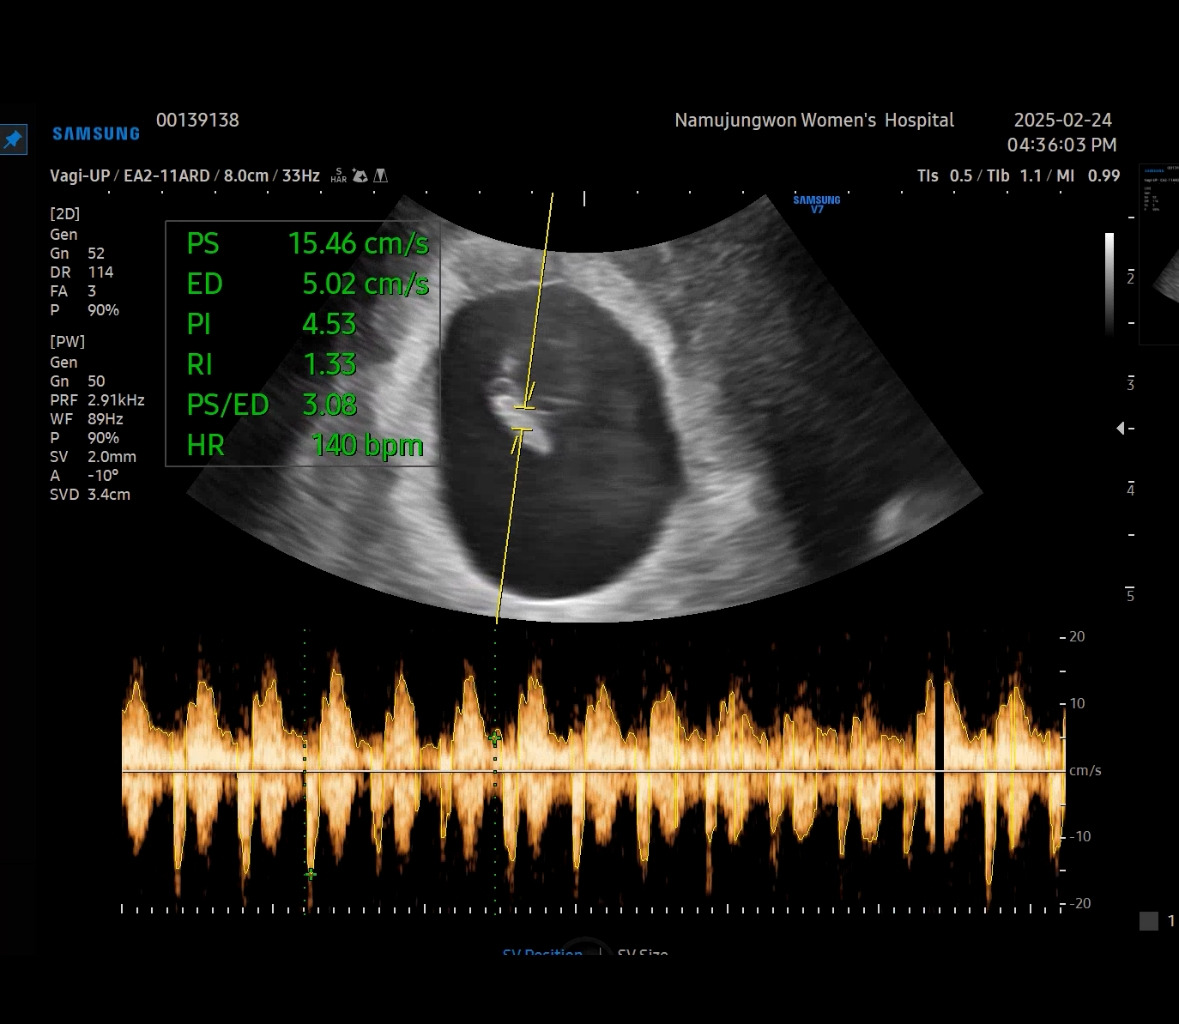

심장소리를 잡고 엄청 볼륨을 높여 주셔서 순간 울컥하는 마음에 눈물이 고였다. 신기하다. 1센티가 안 되는 저 꼬물이가 심장이 뛰고 있다는 게.

8주 차 6일. 아기가 하리보 젤리를 닮았다고 해서 젤리곰 시기라고 많이 부른다. 의사 선생님이 하리곰 모양을 예쁘게 잡아서 머리, 팔, 다리, 심장을 알려주셨다.

아참! 이때부터 입덧약을 매일 저녁 2알 받아먹었다. 아마도 입덧이 점점 심해진 것인지 먹어도 저녁 울렁거림은 줄어들진 않았다. 다행히도 아침, 점심때까지는 입덧하기 전의 평소와 같았다.